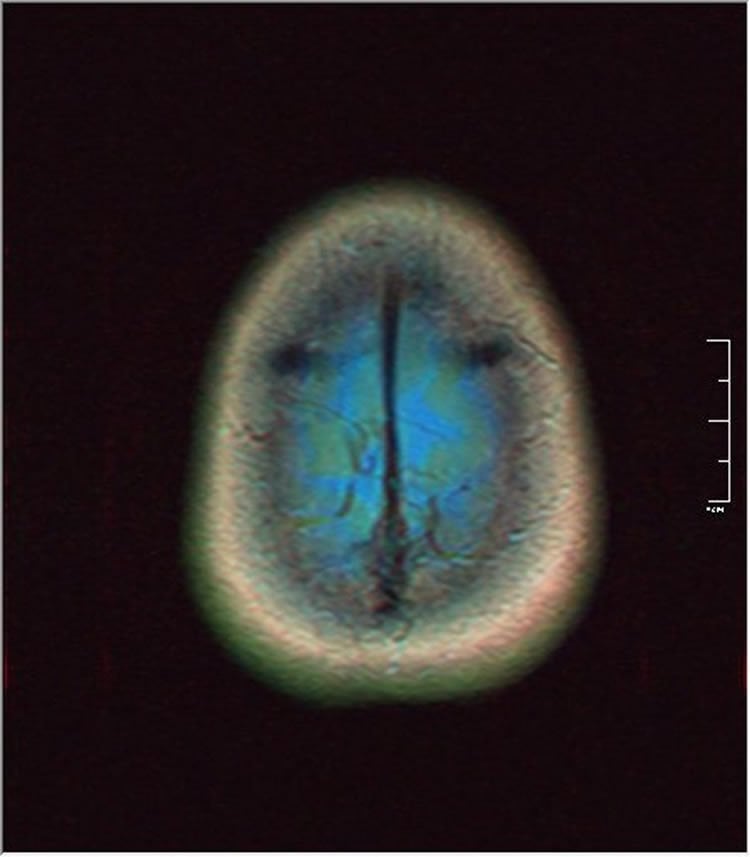

Image Credit: The image is credited to Nevit Dilmen and is licensed CC BY SA 3.0.